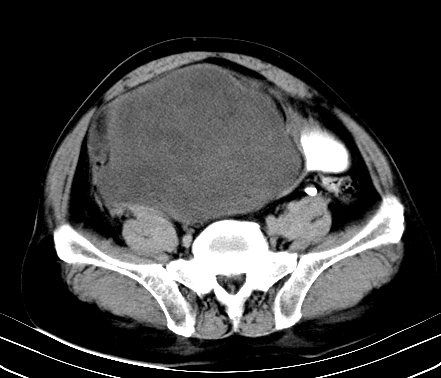

标题: CT19729B:男,74岁,因腿疼就诊,查体触腹部肿物,

增强扫描

静脉期

延时期

【ct表现】

1、肿块巨大,往往位于腹膜后,长大后才引起症状而就诊;那么位于腹膜后的肿瘤80%为恶性肿瘤。

2、实性肿瘤,增强扫描轻度不均强化,实性肿瘤一般不是好东西。

3、肿瘤边缘似见少许脂肪样密度。

4、腹膜后未见肿大淋巴结,但肿瘤于临近的肠管及组织接触紧密。

【诊断】

腹部占位,考虑位于腹膜后的恶性肿瘤,脂肪肉瘤(实体型)可能性大。

术后病理结果:腹膜后脂肪肉瘤。